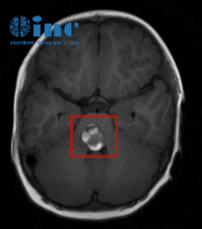

本来抱着应该就是小病小痛开点药就好了,直到医生听完症状描述后建议给伊伊做一个核磁检查,一家人的心突然揪了起来,较后核磁检查提示伊伊为脑干海绵状血管瘤,孩子持续20多天的双眼斜视、不自主扭头、走路不稳等症状是由于脑干海绵状血管瘤破裂出血所致。

(伊伊的脑干海绵状血管瘤病变位置)